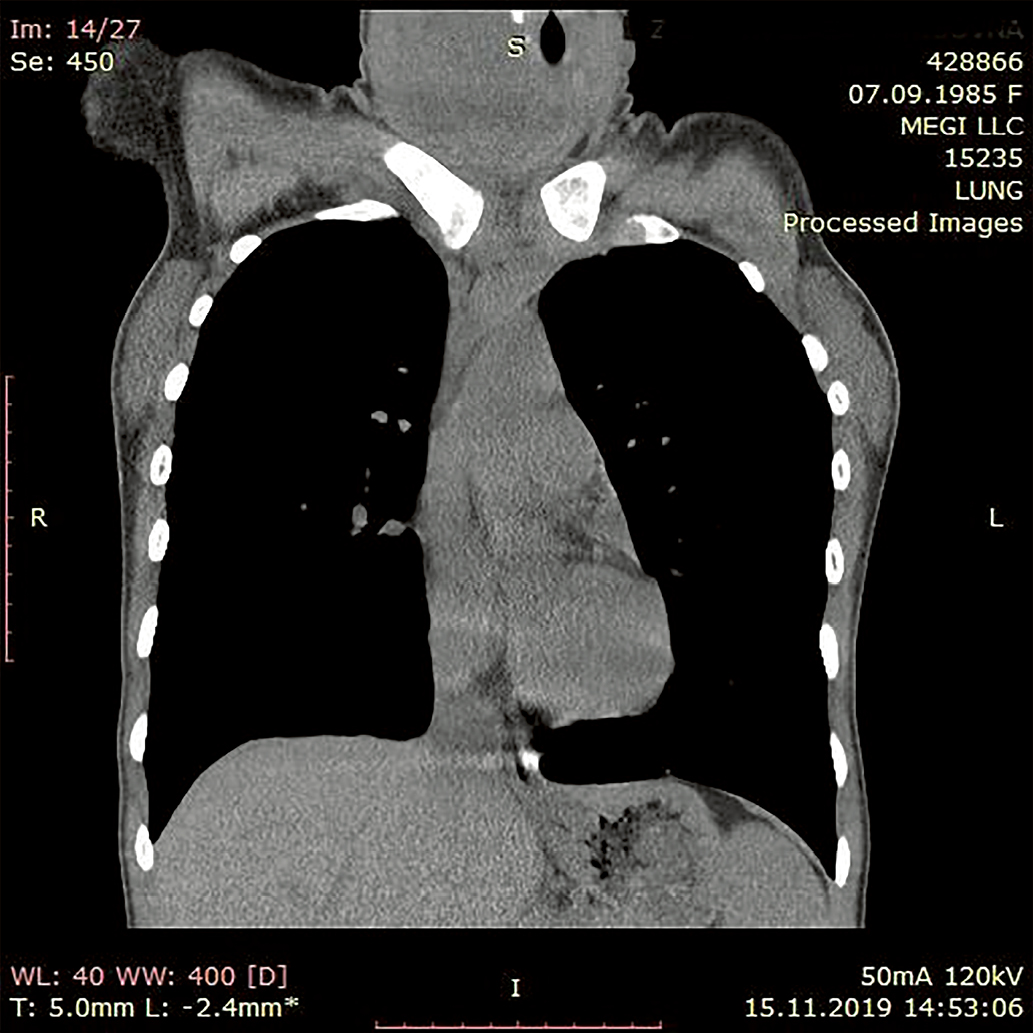

2. Рисунок 2. КТ органов шеи и средостения пациентки до лечения (передняя проекция).

Тема

Тип Прочее

Посмотреть (470KB)

Метаданные ▾

3. Рисунок 3. КТ органов шеи и средостения пациентки до лечения (передняя проекция).

Посмотреть (403KB)

4. Рисунок 4. КТ органов шеи и средостения пациентки до лечения (боковая проекция).

Посмотреть (538KB)